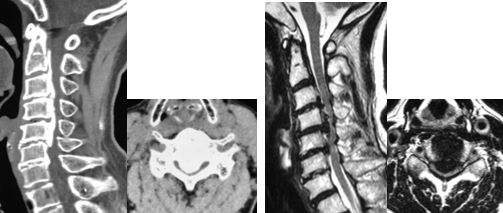

手術前のCTおよびMRIでは、椎体の後ろにある骨化した後縦靭帯が脊柱管内に大きく占拠し、脊髄を強く圧迫しています。

前方から椎体切除および骨化巣の浮上術を行い、代わりに金属製のケージを設置しました。非常に高度な狭窄であったため、後方からも除圧を追加し、頚椎のカーブを維持するためにスクリューとロッドによる固定を行いました。術後、神経症状は著明に改善しています。